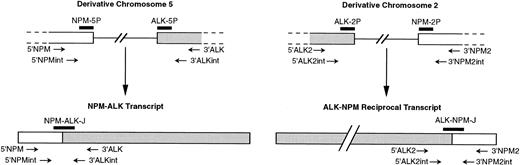

Schematic diagram of NPM and ALK regions rearranged by t(2;5) (according to Ladanyi and Cavalchire55) and mRNA. NPM and ALK exons, whose normal sizes are unknown, are shown as open boxes, and single lines represent introns. The relative approximate positions of PCR primers and probes used in our study are indicated.

Schematic diagram of NPM and ALK regions rearranged by t(2;5) (according to Ladanyi and Cavalchire55) and mRNA. NPM and ALK exons, whose normal sizes are unknown, are shown as open boxes, and single lines represent introns. The relative approximate positions of PCR primers and probes used in our study are indicated.